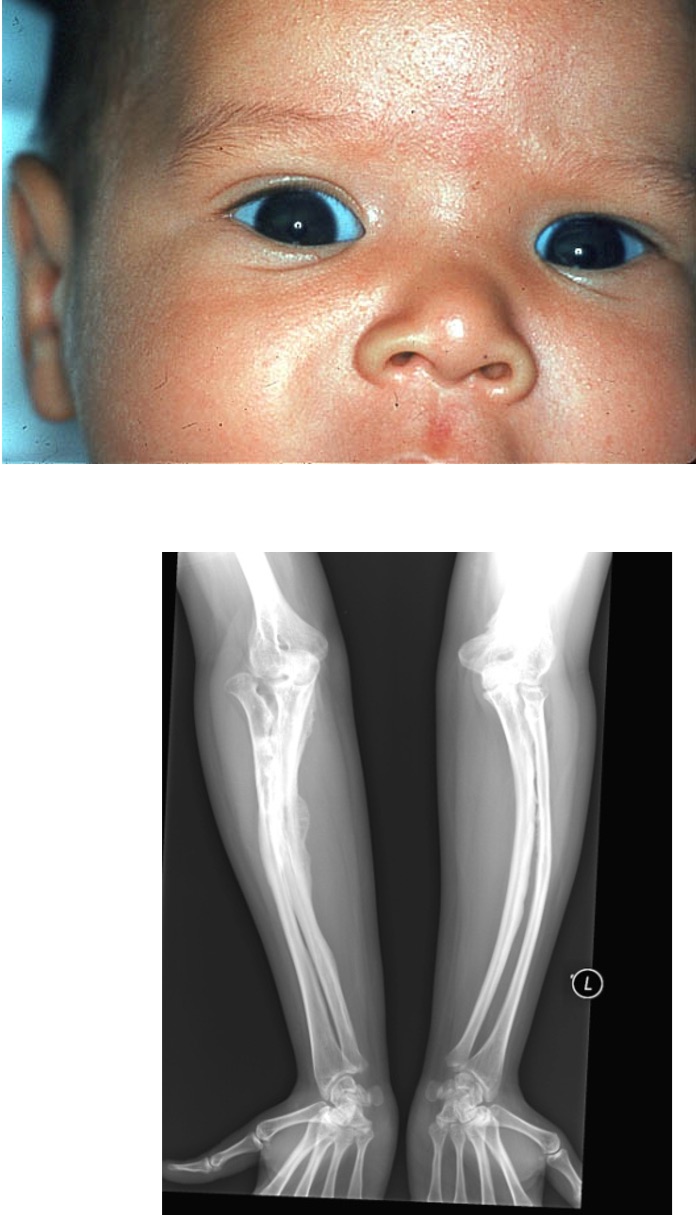

What is osteogenesis imperfecta?

it is an inherited disorder (brittle bone disease)

What are the clinical manifestations of osteogenesis imperfecta?

frequent fractures

blue sclera

thin, soft skin

short stature

hearing loss

delay in walking

What can osteogenesis imperfecta be mistaken for?

it can be mistaken for child abuseÂ

What are the medical managements for osteogenesis imperfecta?

no cure, only medication that can slow the release of calcium from bones (IV pamidronate)

physical therapy can help strengthen muscles and support bone density

casting, bracing, or splinting

What are some nursing managements we can do for osteogenesis imperfecta?

sliding diapers under instead

of lifting legs

use blankets for positioning

non-weight baring activities (swimming)